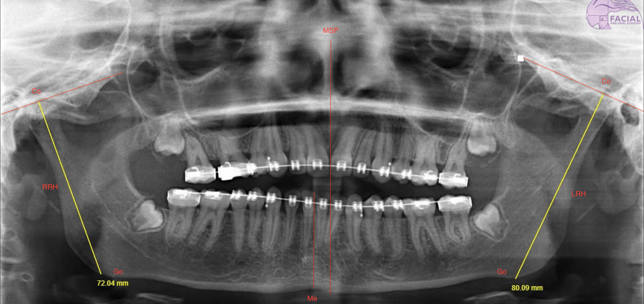

Maxillofacial Surgery , Aesthetic Medicine , Facial Plastic Surgery

Mandibular asymmetry: Importance of personalised treatment